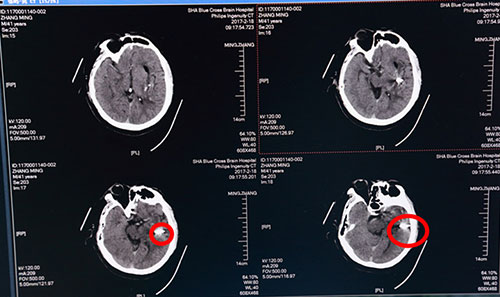

当日,李振并主任急诊在局麻下为张先生施行了“颅内血肿微创清除术”。术中根据头颅CT片三维定位,取左侧颞部为穿刺点,用一次性血肿穿刺针直达血肿中心,接引流管,抽出暗红色血块40多ML。

术后第二日头颅CT:血肿基本清除,红圈内白色光点为穿刺针